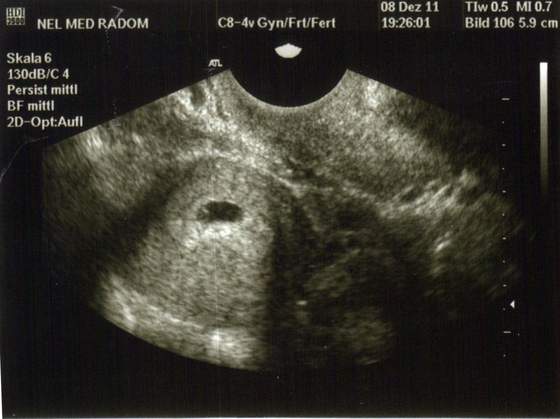

Moje pierwsze, zrobione 2 tygodnie temu. Dziś myślę, że będzie kolejne :)

A ja byłam już 3 razy u ginka, i juz 3 zdjecia zrobił w tym własnie za pierwszym razem pęcherzyk, ale nie dał mi zdjęcia buuu:( a chciałam męzowi pokazać, powiedzial że to jeszcze mało widać, ale jednak mała fasoleczka nasza była:-) no ale następnym razem to juz musi dać foto!

To i ja dołączam do was w końcu, maleństwo potwierdzone usg 29.12:)

Łobuziak nam stracha napędził, bo schował serduszko i lekarz dopiero dopochwowym znalazł, biło jak szalone:)